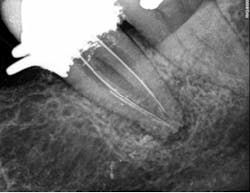

Figures 4 through 6 demonstrate a complex nonsurgical retreatment that involved post removal, cleaning and shaping the untreated canal, and obturation. Unfortunately, retreatment is not a realistic option for a variety of reasons.